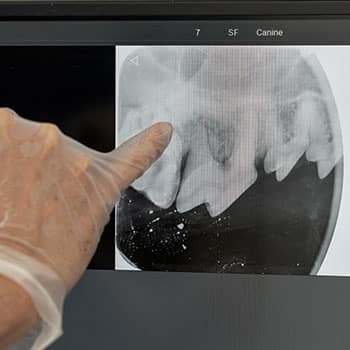

Dental X-rays

Most tooth problems in dogs and cats occur below the gum line, where you cannot see them. Dental X-rays provide focused images that allow us to see each tooth’s entire structure, including the root, and identify common issues, including tooth root abscesses, bone loss, tooth resorption, and unerupted teeth. Our veterinary team performs full-mouth dental X-rays each time your pet is anesthetized for a dental cleaning or oral surgery.